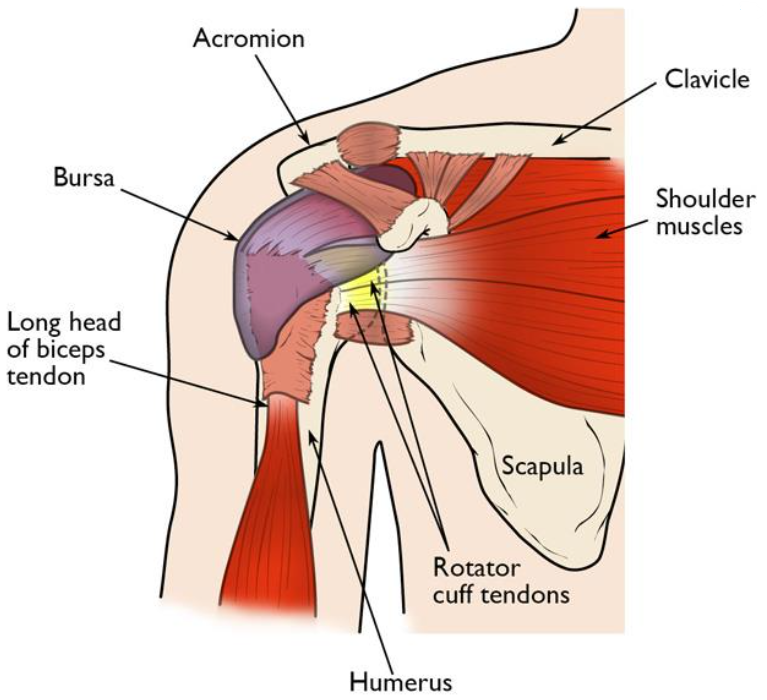

شانه درد یکی از مشکلات شایع است که میتواند به دلیل آسیبدیدگی مفاصل، عضلات، تاندونها، یا دیگر ساختارهای اطراف شانه رخ دهد. درد شانه ممکن است حاد یا مزمن باشد و میتواند زندگی روزمره افراد را تحت تأثیر قرار دهد.